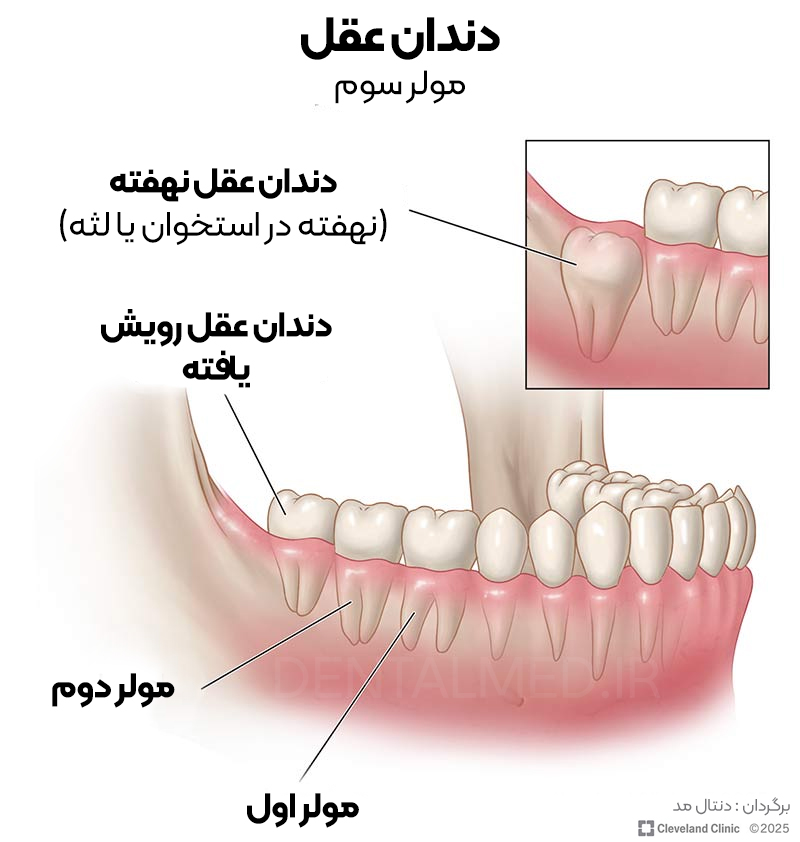

دندان های عقل آخرین مجموعه از دندانهای دائمی هستند که در دهان رویش پیدا میکنند. نام دیگر آنها «آسیاب سوم» است. این دندانها در انتهای دهان، در قسمت عقب قرار دارند.

گاهی دندانهای عقل به درستی رشد میکنند و هیچ مشکلی ایجاد نمیکنند. اما در بسیاری از موارد، این دندانها در لثه یا استخوان فک گیر میکنند و رویش نمییابند (دندان عقل نهفته). در چنین شرایطی ممکن است دچار عفونت، پوسیدگی، بیماری لثه و دیگر مشکلات دهانی شوید. به همین دلیل است که بسیاری از دندانپزشکان توصیه به کشیدن دندانهای عقل میکنند.

دندانهای عقل در انتهای دهان، درست پشت دندانهای آسیای دوم قرار میگیرند. افرادی که هر چهار دندان عقل را دارند، در هر ربع از دهانشان یکی دارند: بالا چپ، پایین چپ، بالا راست و پایین راست.

دندانهای عقل از نظر ظاهری شبیه سایر دندانهای آسیای دهان هستند. اغلب دارای دو یا سه ریشه هستند، اما برخی از آنها ممکن است چهار ریشه داشته باشند.